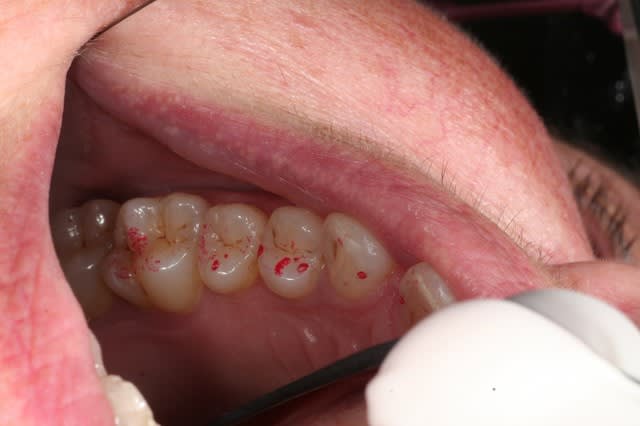

voilà les images en OIM.

Oim bas droite xvndix - Eugenol

Oim bas gauche d4ewj0 - Eugenol

hé hé hé tu as chargé les implants je suppose ? tu as un blocage en violet à droite de façon quasi certaine, regarde les contacts que tu as en 14 et 15, voire 16...

en Vasalva elle doit avoir dur de déboucher l'oreille droite lors de la déglutition subséquente, et maintenant la question fatidique, as-tu les fitres colorés ? si c'est négatif alors je peux t'envoyer une paire de lunettes avec filtres et un mode d'emploi, je peux aussi te guider par téléphone quand tu reverras ta patiente... mais d'après ce que tu me dis je penche pour une surcharge sur 14, voire 13 ou 15, je suppose que tu as réglé l'occlusion avec un contact léger sur 45 et 46, d'où la surcharge possible sur 15, 14 et 13, avec une préférence sur 14

C'est ainsi que je l'avais imaginé, reprends sur les prémolaires au soflex rouge gros grains ou au carborandum vert bouteille... Quand je regarde la panoramique dans son ensemble, je vois la perte des dents à droite, je vois la perte osseuse au niveau des molaires maxillaires droites, je vois les diastèmes par ci par là, je me dis qu'elle presse les dents la vieille dame, je me dis aussi qu'il doit y avoir nécessairement surcharge quelque part, les photos que tu me montres tendent à incriminer les premières prémolaires maixillaires, commence par là tu ne peux pas te tromper, après correction fais la déglutir deux trois fois, fais lui avaler de l'eau, dis lui de faire une vasalva histoire de voir si les delta de pression se lèvent ensuite lors de la nouvelle pim suivie d'une déglutition redevenue normalement fonctionnelle au niveau tubaire, ensuite tu devrais pouvoir disposer des filtres pour aller plus finement dans l'examen de la fonctionnalité des cochlées...